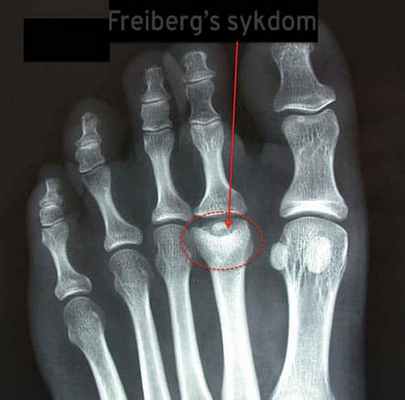

Келера болезнь II (Фрейберга болезнь) — остеохондропатия, асептический некроз головок плюсневых костей (рис. 350, на схеме — II, реже — III-IV). Болезнь имеет этапность течения.

Рис. 350. Динамика изменения при остеохондропатии головки плюсневой кости: А — уплотнение тени головки плюсневой кости (некроз); б — тень более плотная, отмечается уплощение головки, увеличение высоты суставной щели — стадия импрессионного перелома; В — стадия фрагментации, головка представлена отдельными фрагментами; Г— восстановление структуры, деформация головки плюсневой кости; Д — исход заболевания — деформирующий артроз плюснефалангового сустава

- На картинке выше мы видим остеонекроз (отмирание костной ткани) второй плюсневой кости. Характерный признак болезни Фрейберга.